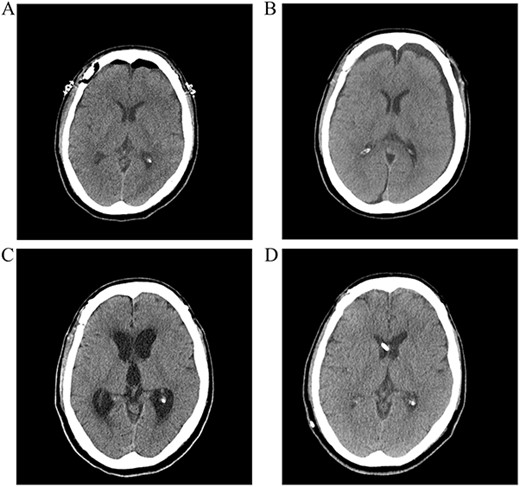

A postoperative computed tomography (CT) scan the day after surgery showed no postoperative hemorrhage (Fig. 1A). A postoperative CT angiogram showed successful clipping of both aneurysms. The patient was discharged on postoperative day 9. On postoperative day 13, the patient visited our clinic with a complaint of a severe headache. A CT scan showed subgaleal fluid collection on the left side, and scanty bilateral subdural fluid collection (Fig. 1B). We performed a lumbar tap of the cerebrospinal fluid (CSF), and the subarachnoid pressure was 12 cm H2O. The CSF was clear, and protein and glucose concentrations were 150.8 mg/dl and 52 mg/dl, respectively. The white blood cell count was 0 lymphocytes/mm3, and no microorganisms were identified in any culture. Blood tests showed no inflammatory reactions, such as leukocytosis or elevated C-reactive protein levels. On postoperative day 26, a follow-up CT scan showed improvement in the collection of the subgaleal and subdural fluids, and the headache subsided. However, the patient presented with gait disturbance and cognitive impairment 2 weeks later. A CT scan showed ventricular enlargement, and cisternography confirmed type IV hydrocephalus (Fig. 1C). The patient underwent permanent shunt placement and was discharged following good recovery (Fig. 1D).

(A) Postoperative CT scan showing no subarachnoid or intraventricular hemorrhages. (B) Bilateral subdural fluid collection on postoperative day 13 CT scan. (C) Increased ventricle size by day 26. The patients developed symptoms of hydrocephalus. (D) A ventriculoperitoneal shunt was placed on day 47. Ventricle size decreased and clinical signs of hydrocephalus improved.